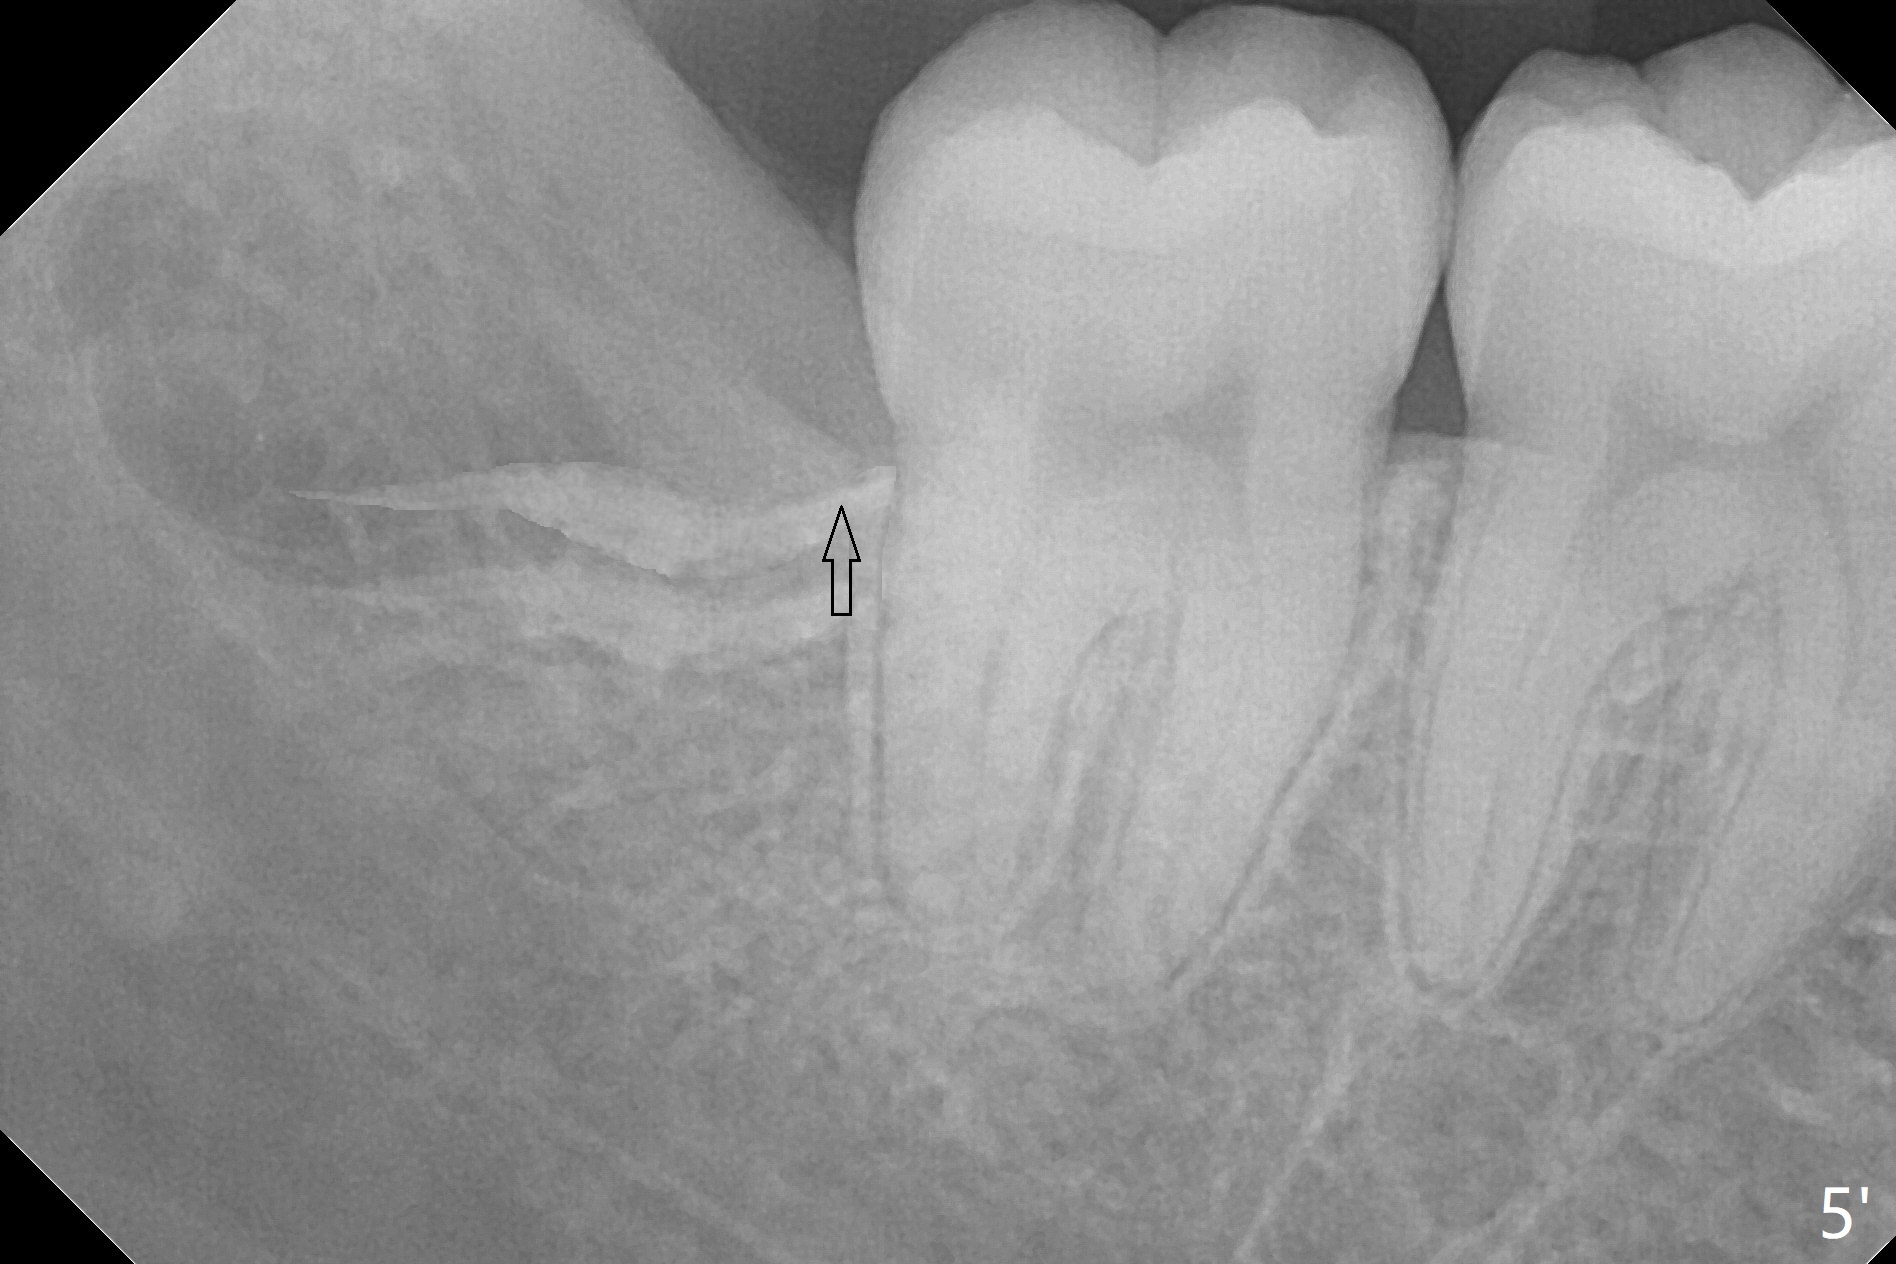

In fact the tooth #32 is extracted first; the defect involves the distobuccal aspect of the tooth #31 (Fig.4 *). An intraop PA is taken after extraction to confirm whether a broken surgical fissure bur tip retains or not; the distal lamina dura of #31 is low (Fig.5 *). It is expected to increase after cocktail bone graft (Fig.5' arrow). As planned, the bone cement (Fig.6 C) and allograft (G) are placed in the distal and mesial portions of the socket; between them is Osteogen Plug (O). Another piece of Osteogen Plug (as collagen membrane for bone graft) is placed on the top of the socket before suturing with 4-0 Plain Gut (Fig.7,7' O). Also note the bone graft being placed distobuccal (CT study) to #31 (Fig.7' red dashed line) to reduce possibility of future periodontitis. The patient returns 15 days postop with chief complaint of mild pain since extraction, although the wound looks normal. The transverse cortex connecting to the lamina dura (Fig.5 *) is obliterated when allograft is placed (Fig.7 G). The part of the graft remains in place 1 month postop (Fig.9) in spite of wound dehiscence (Fig.8). The bone graft loss is indicated by the fact of the reappearance of the transverse cortex (Fig.9). In the same appointment, the tooth #17 (Fig.10) is being extracted (Fig.11), leaving a defect mesiobuccal (Fig.12 *) to distal (curette). Part of Osteogen plug (Fig.13 O) is stretched to cover the mesially placed allograft (Fig.14 G). One quarter of Collagen plug is placed over the Osteogen plug (Fig.13 O) before 4-0 PGA suturing. There is bone regeneration 1 year postop (Fig.15,16).